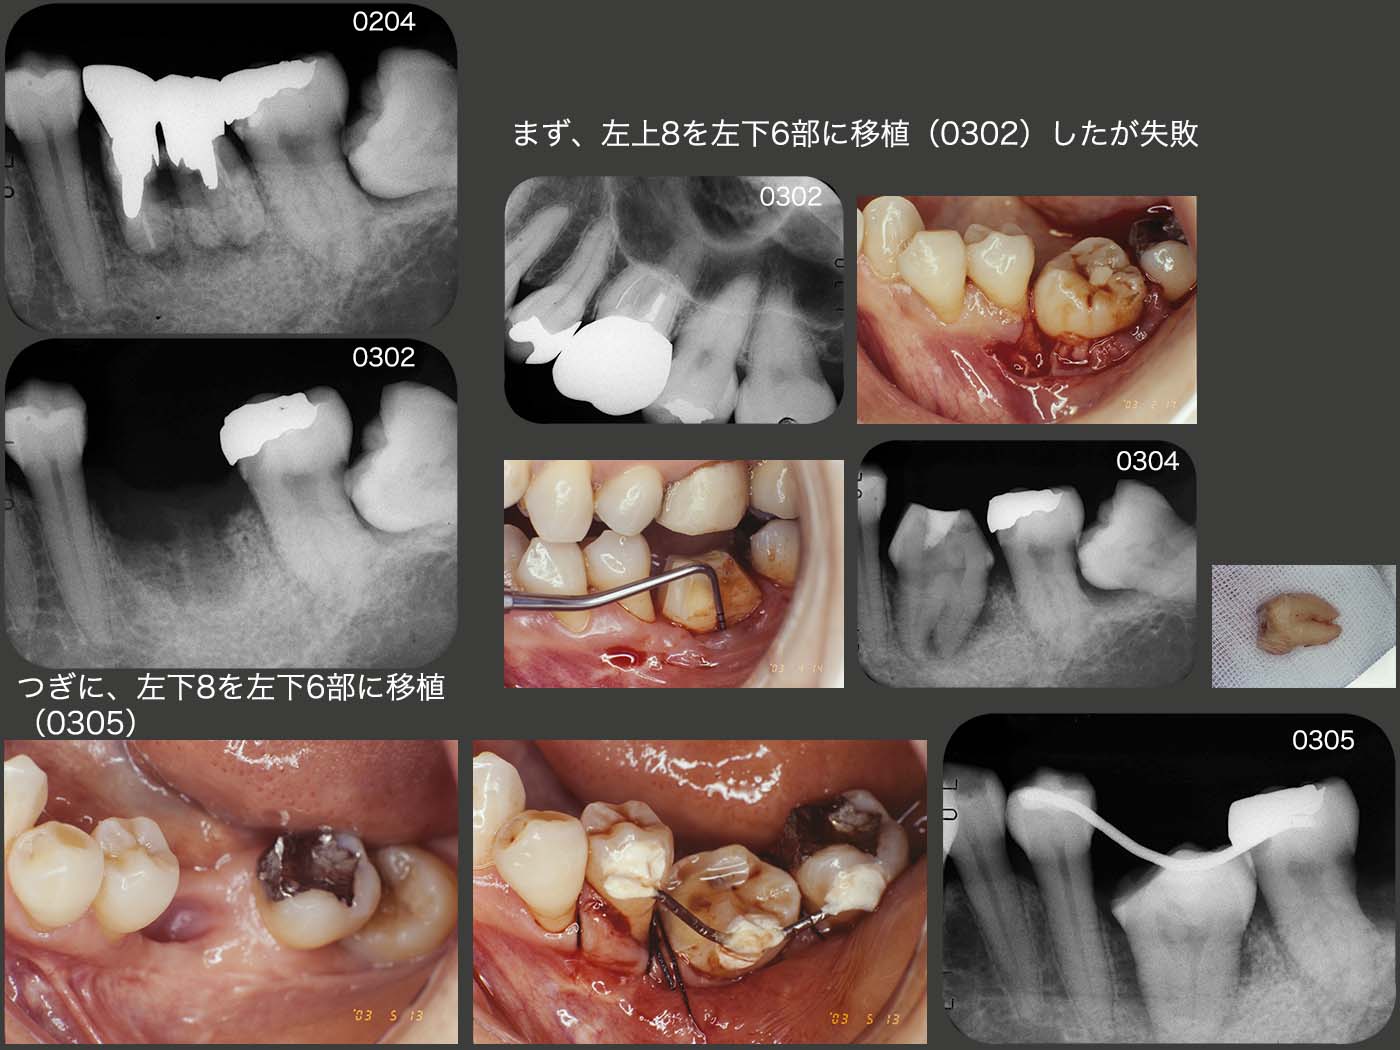

2003年1月,左下6を抜去し,2月にまず抜歯の容易な左上8を移植した.しかしドナー歯は2根あり,根分岐部が上手く付着しなかった.4月にこの歯を抜去し,5月に左下8を再度移植した.埋入深度を深くするために,ドナー歯の歯冠幅径を小さくする必要があるが,削去することで歯根膜を汚染することは避けたかったので,頰側に傾斜埋入した.